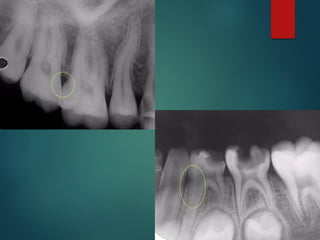

Quiste

 Area radiolúcida

 Redonda u oval unilocular

 Bordes bien definidos

 Habitualmente

corticalizada

 Tamaño mayor a 1 cm

 Pueden expandirse a seno

maxilar

 Pueden producir rizálisis en

dientes adyacentes

Osteítis

Osteitis

 Límites difusos

 Tamaño variable

 Diente infectado

 Concepto radiográfico